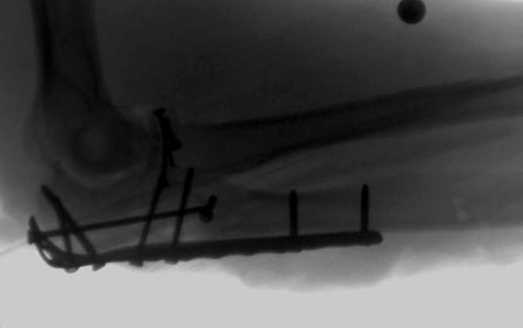

2 вариант

перелом локтевого отростка с переломом головки лучевой кости

(использованы 2 мм шурупы)